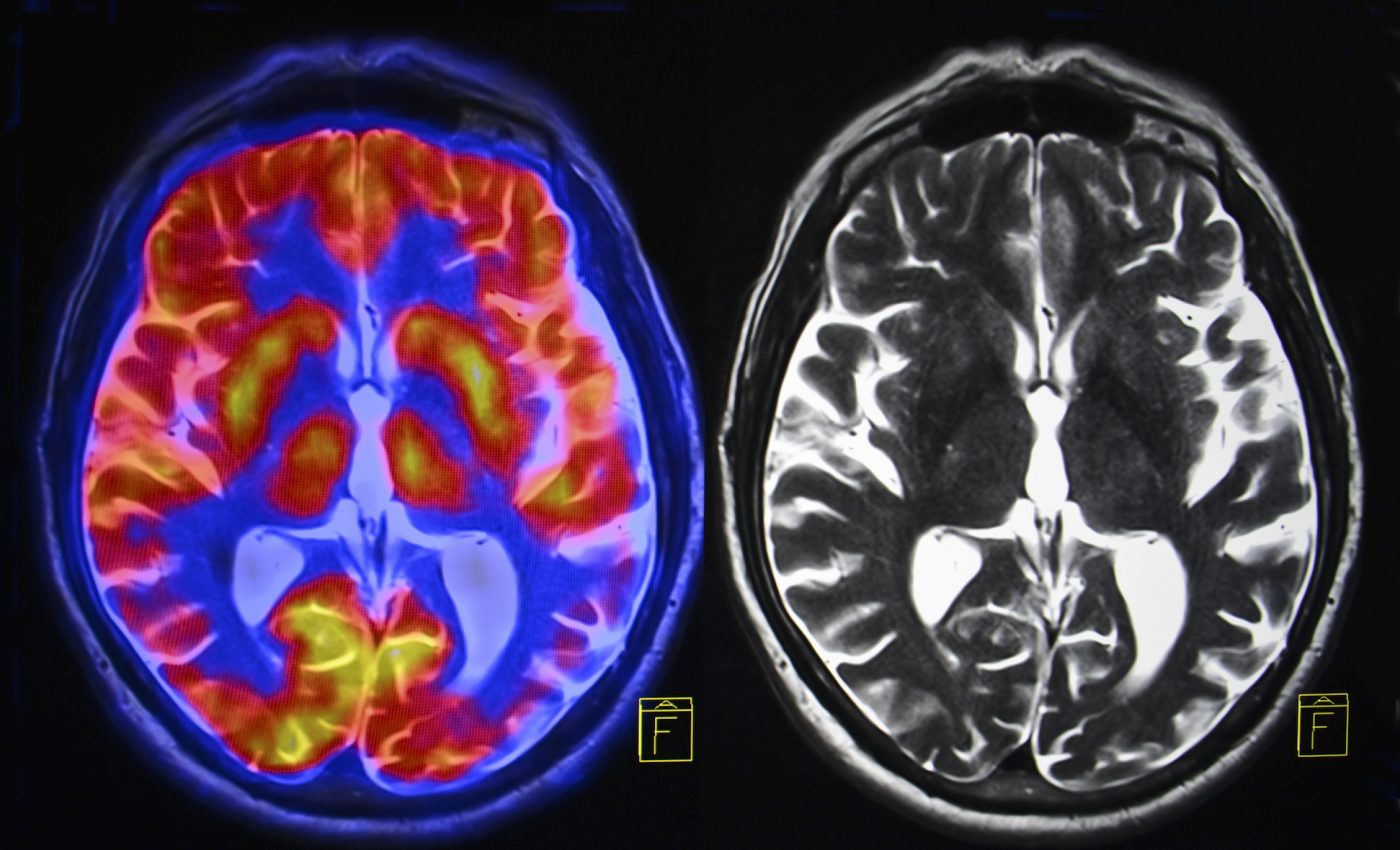

The researchers performed scans using functional near-infrared spectroscopy (fNIRS), which is a relatively new neuroimaging technique that is considered to be promising for future scientific studies because it is non-invasive, inexpensive, and portable. Using fNIRS, brain activity is measured through responses that are associated with neuron behavior.

After the trials, the researchers used machine learning to analyze the scans. The analysis revealed that novice surgeons exhibited increased activity in different areas of the brain compared to the expert surgeons.

Brain activity spiked in the prefrontal cortex – which is responsible for planning complex behavior – for both novices and unskilled medical students. On the other hand, activity in the primary motor cortex – which controls the execution of movement – increased among experienced surgeons while decreasing in the other groups.